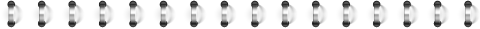

另外,声像图中的“不规则边缘”是指结节与腺体实质之间呈不规则的小叶状、浸润性或毛刺状边界,对于恶性结节的诊断具有较高的特异性(图14~16)。 因此,“边界不合逻辑”与“边界不规则”的概念和诊断价值明显不同。

![图片[8]-一份甲状腺超声报告到手,从哪看起?-首码网-网上创业赚钱首码项目发布推广平台](https://mmbiz.qpic.cn/mmbiz_jpg/XsibUvKtQsKx2NNYO3iakSag8ODBKyawhYc5vxfJmSpHicVvQYE7qUslicuy3tldia7AnSpLWicZbw3ot578fyibL9VHg/640?wx_fmt.jpeg)

资料来源:人力资源和社会保障部出版的《超声影像报告标准及数据系统分析》